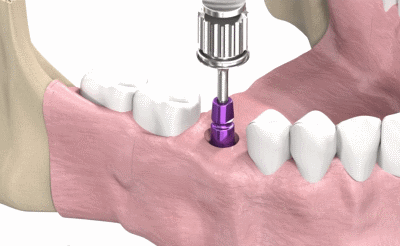

השיטה הטובה ביותר לשחזר שן חסרה היא שתל דנטלי מטטניום. עם התקדמות רפואת השיניים, ישנן טכניקות ושיטות שונות להשתלת שיניים. בפגישת ייעוץ נתאים לכם את השיטה המתאימה ביותר.